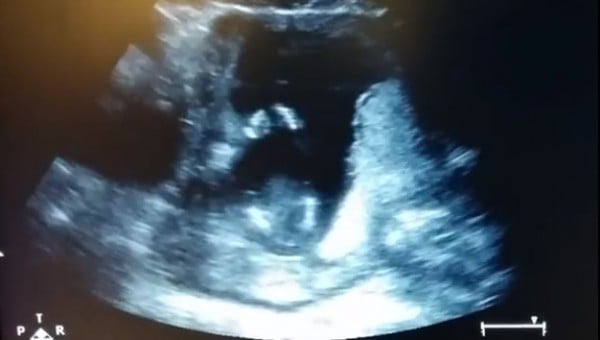

حصد فيديو لجنين يصفق داخل رحم أمه أكثر من مليوني مشاهدة على موقع يوتيوب.

وأثار الفيديو ضجة على مواقع التواصل الاجتماعي، إذ ظهر الجنين يصفق على أنغام الأغنية الإنجليزية "إذا كنت سعيدا صفق بيديك"، والتي كان والده يغنيها في إحدى جلسات التصوير بالأمواج فوق الصوتية.

ونقلت صحيفة مترو البريطانية، عن جين كاردينال والدة الطفل، قولها "إن الفيديو حقيقي، وإن طفلها صفق بالفعل، ولكن ليس على أنغام الأغنية".

وأضافت كاردينال "قام الطبيب بإعادة شريط التسجيل، وبدأ والده في الغناء بشكل متزامن مع تصفيقه، لنحصل على هذا الفيديو المدهش".